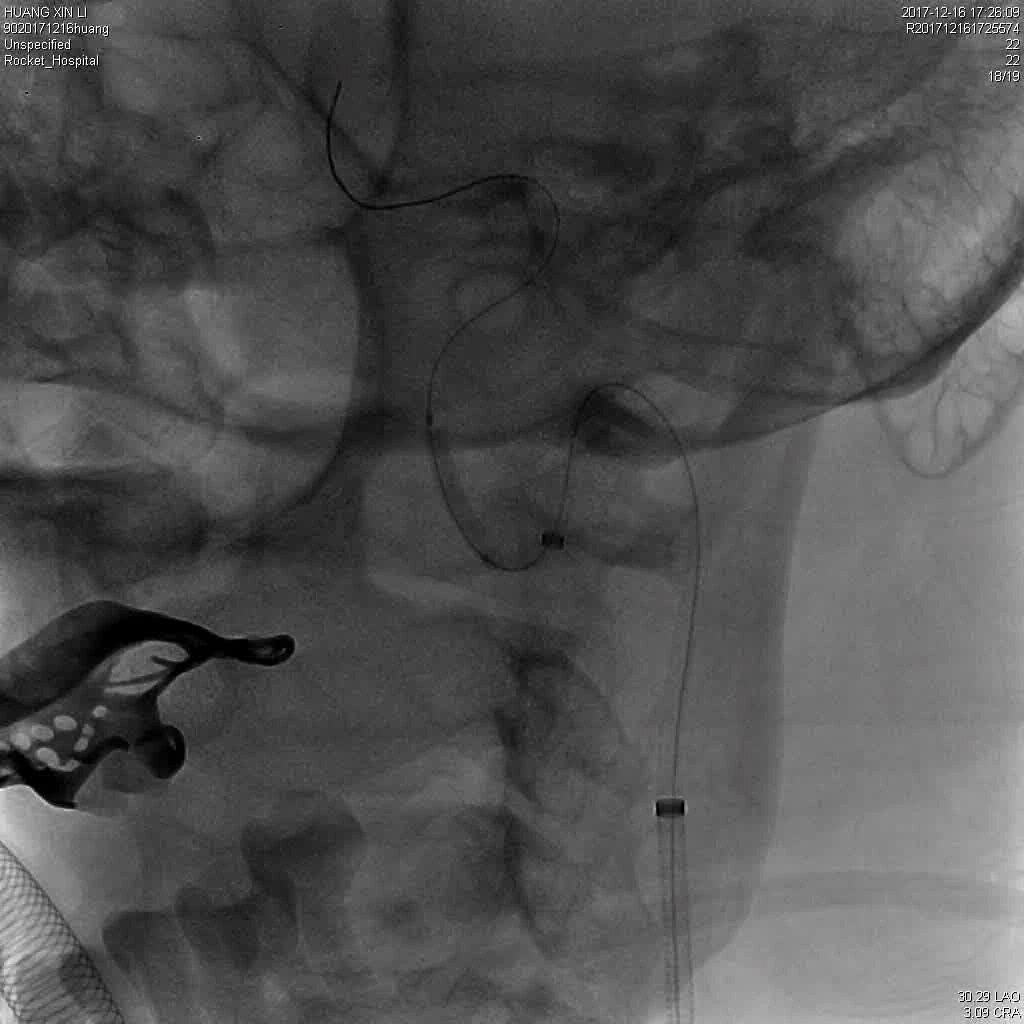

微导管微导丝穿过夹层段,4.0×20mm球囊再次反复贴附夹层段,促进内膜贴壁。

造影观察,管腔狭窄较前好转,血流状态稳定,结束手术。

2018-3-9 日复查CT及CTA,夹层自愈过程中,无栓塞,转康复科行康复训练。